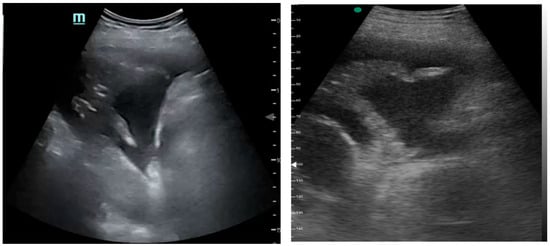

Figure 1, Figure 2 and Figure 3 exhibit characteristic examples of ultrasound still images from the videos captured via a standard ultrasound (left side) and portable handheld device (right side). Quality may slightly differ from that of the videos as these are still images.

Figure 2. Complex pleural effusion with septation.